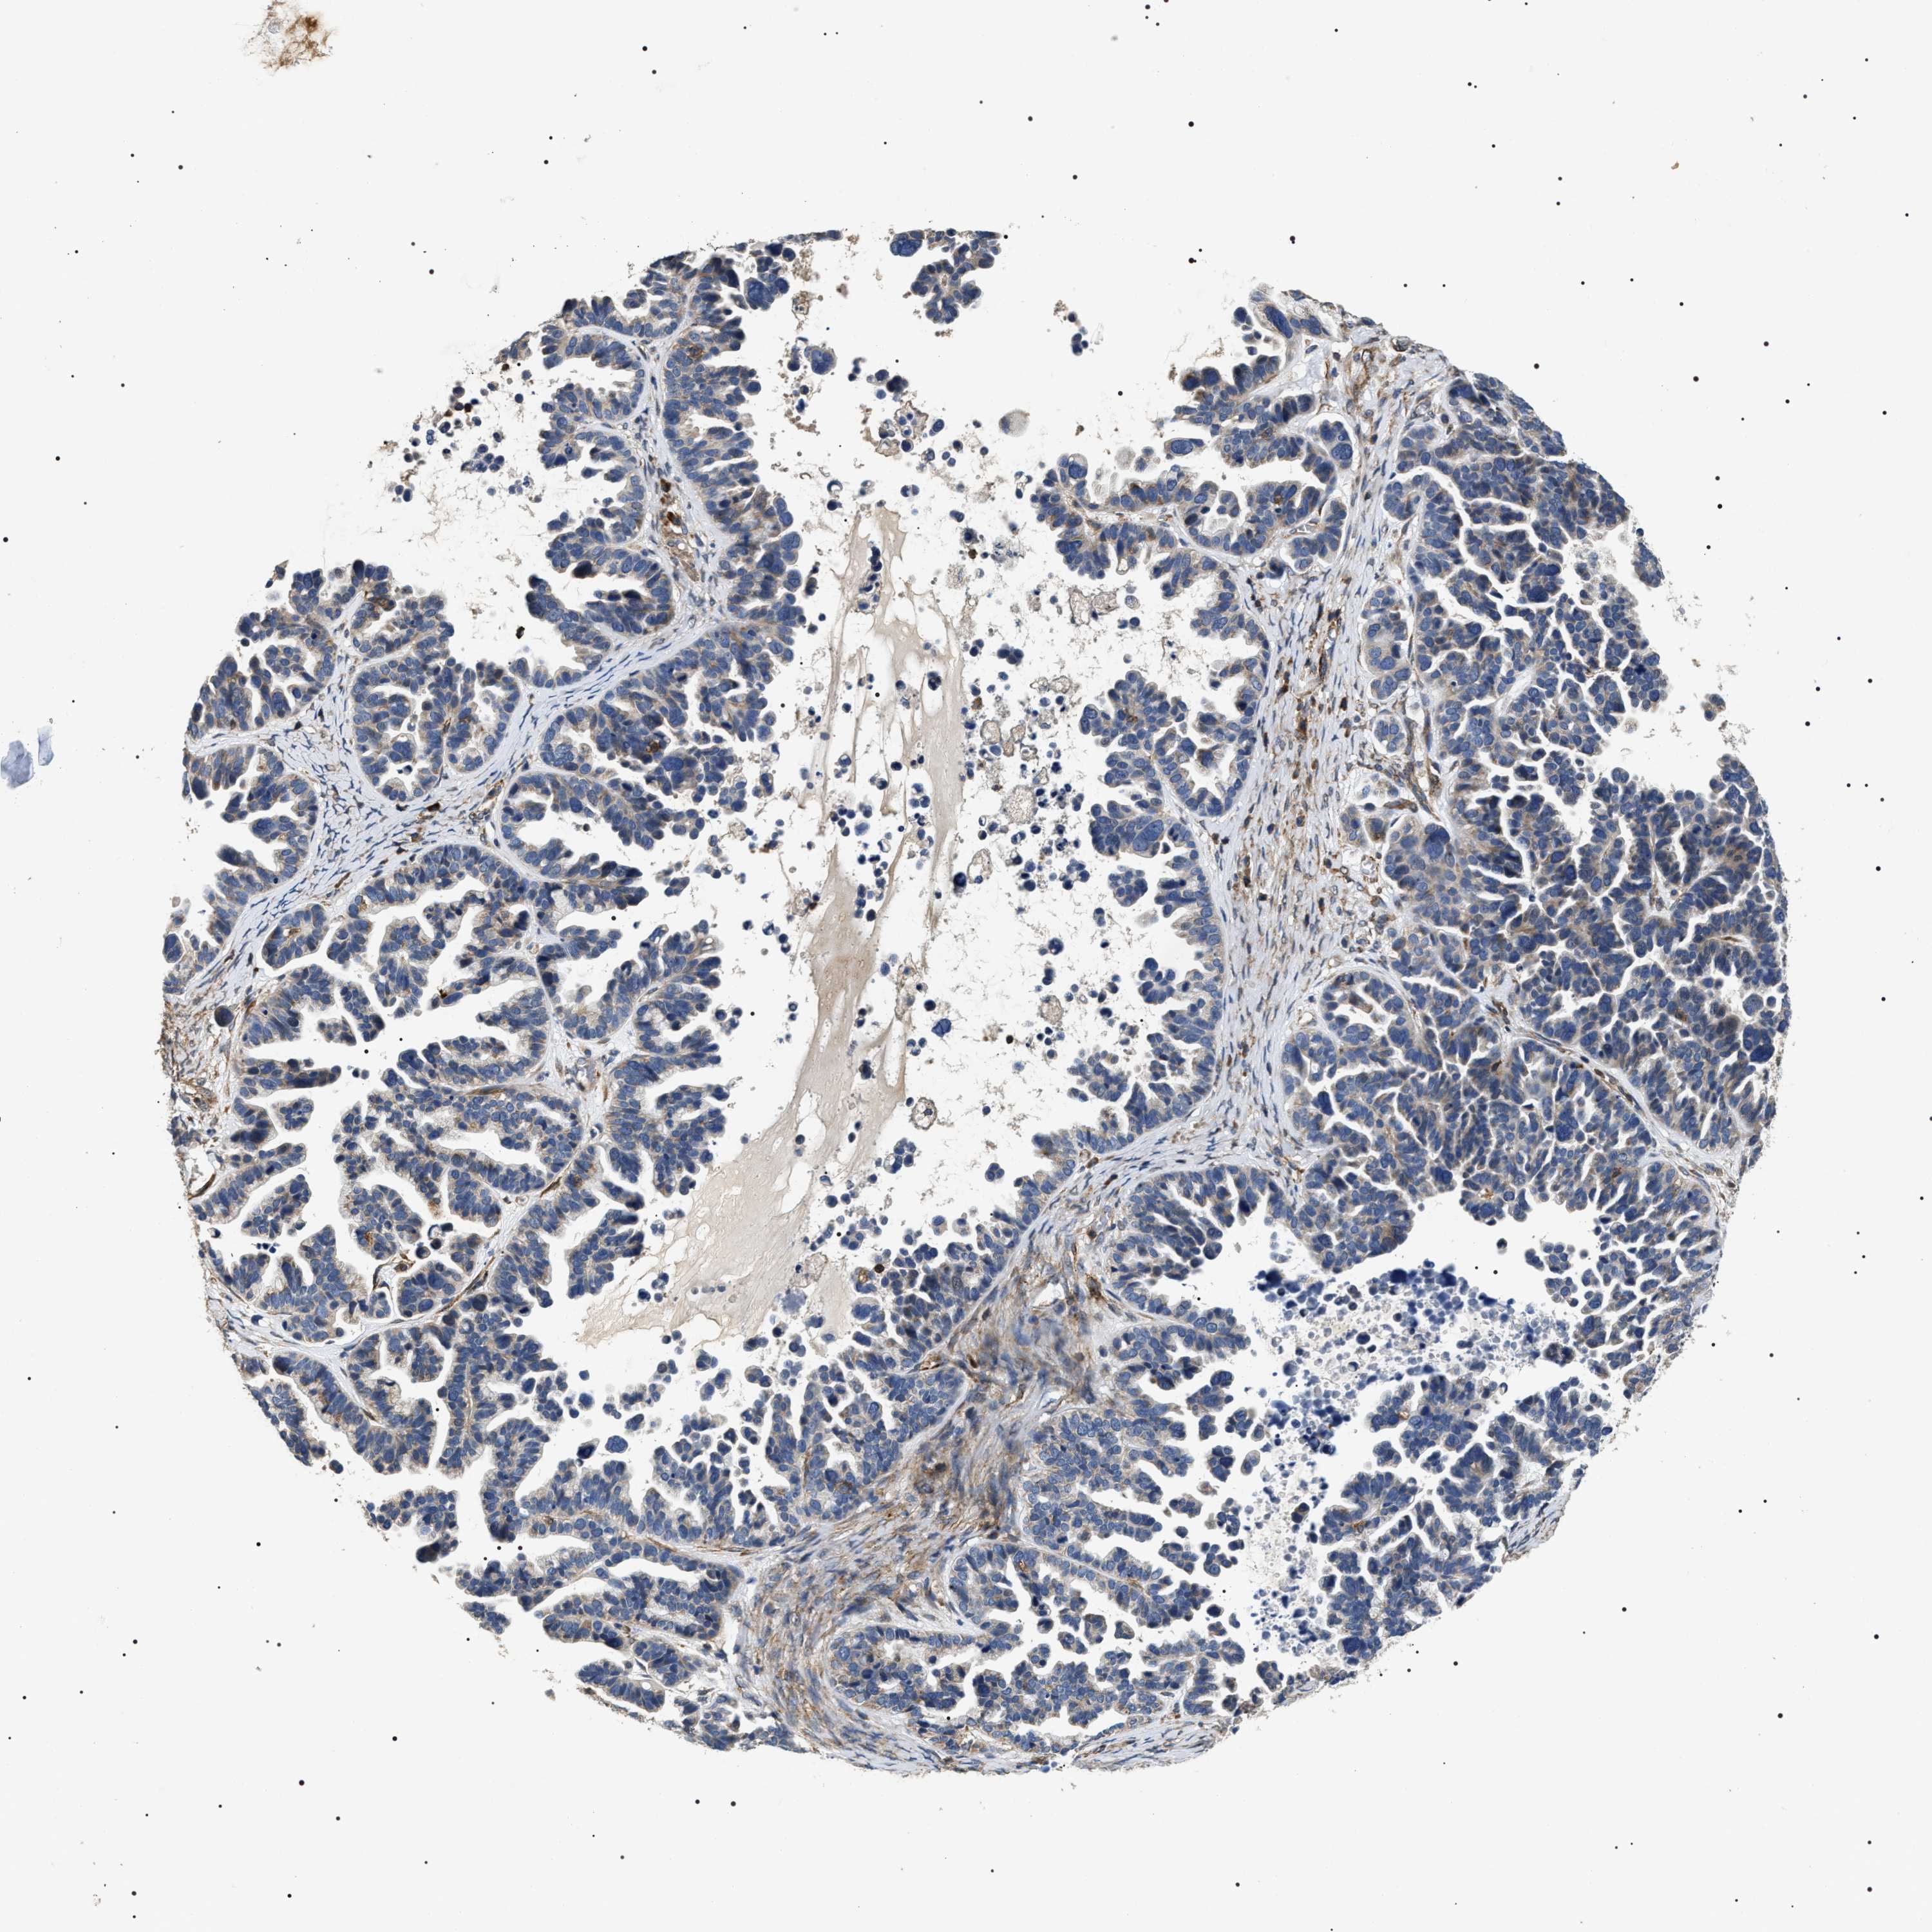

OVARIAN CANCER - Protein expressioni

A mouse-over function shows sample information and annotation data. Click on an image to view it in a full screen mode. Samples can be filtered based on level of antibody staining by selecting one or several of the following categories: high, medium, low and not detected. The assay and annotation is described here.

Note that samples used for immunohistochemistry by the Human Protein Atlas do not correspond to samples in the TCGA dataset.

Antibody stainingi

Antibody staining in the annotated cell types in the current human tissue is reported as not detected, low, medium, or high, based on conventional immunohistochemistry profiling in selected tissues. This score is based on the combination of the staining intensity and fraction of stained cells.

Each image is clickable and will lead to virtual microscopy that enables deeper exploration of all samples and also displays staining intensity scores, fraction scores and subcellular localization as well as patient and tissue information for each sample.

Antibody HPA020386

Staining

High

Medium

Low

Not detected

Intensity

Strong

Moderate

Weak

Negative

Quantity

>75%

75%-25%

<25%

None

Location

Nuclear

Cytoplasmic/membranous

Cytoplasmic/membranous,nuclear

Cystadenocarcinoma, serous, NOS

Carcinoma, endometroid

Cystadenocarcinoma, mucinous, NOS

Carcinoma, NOS